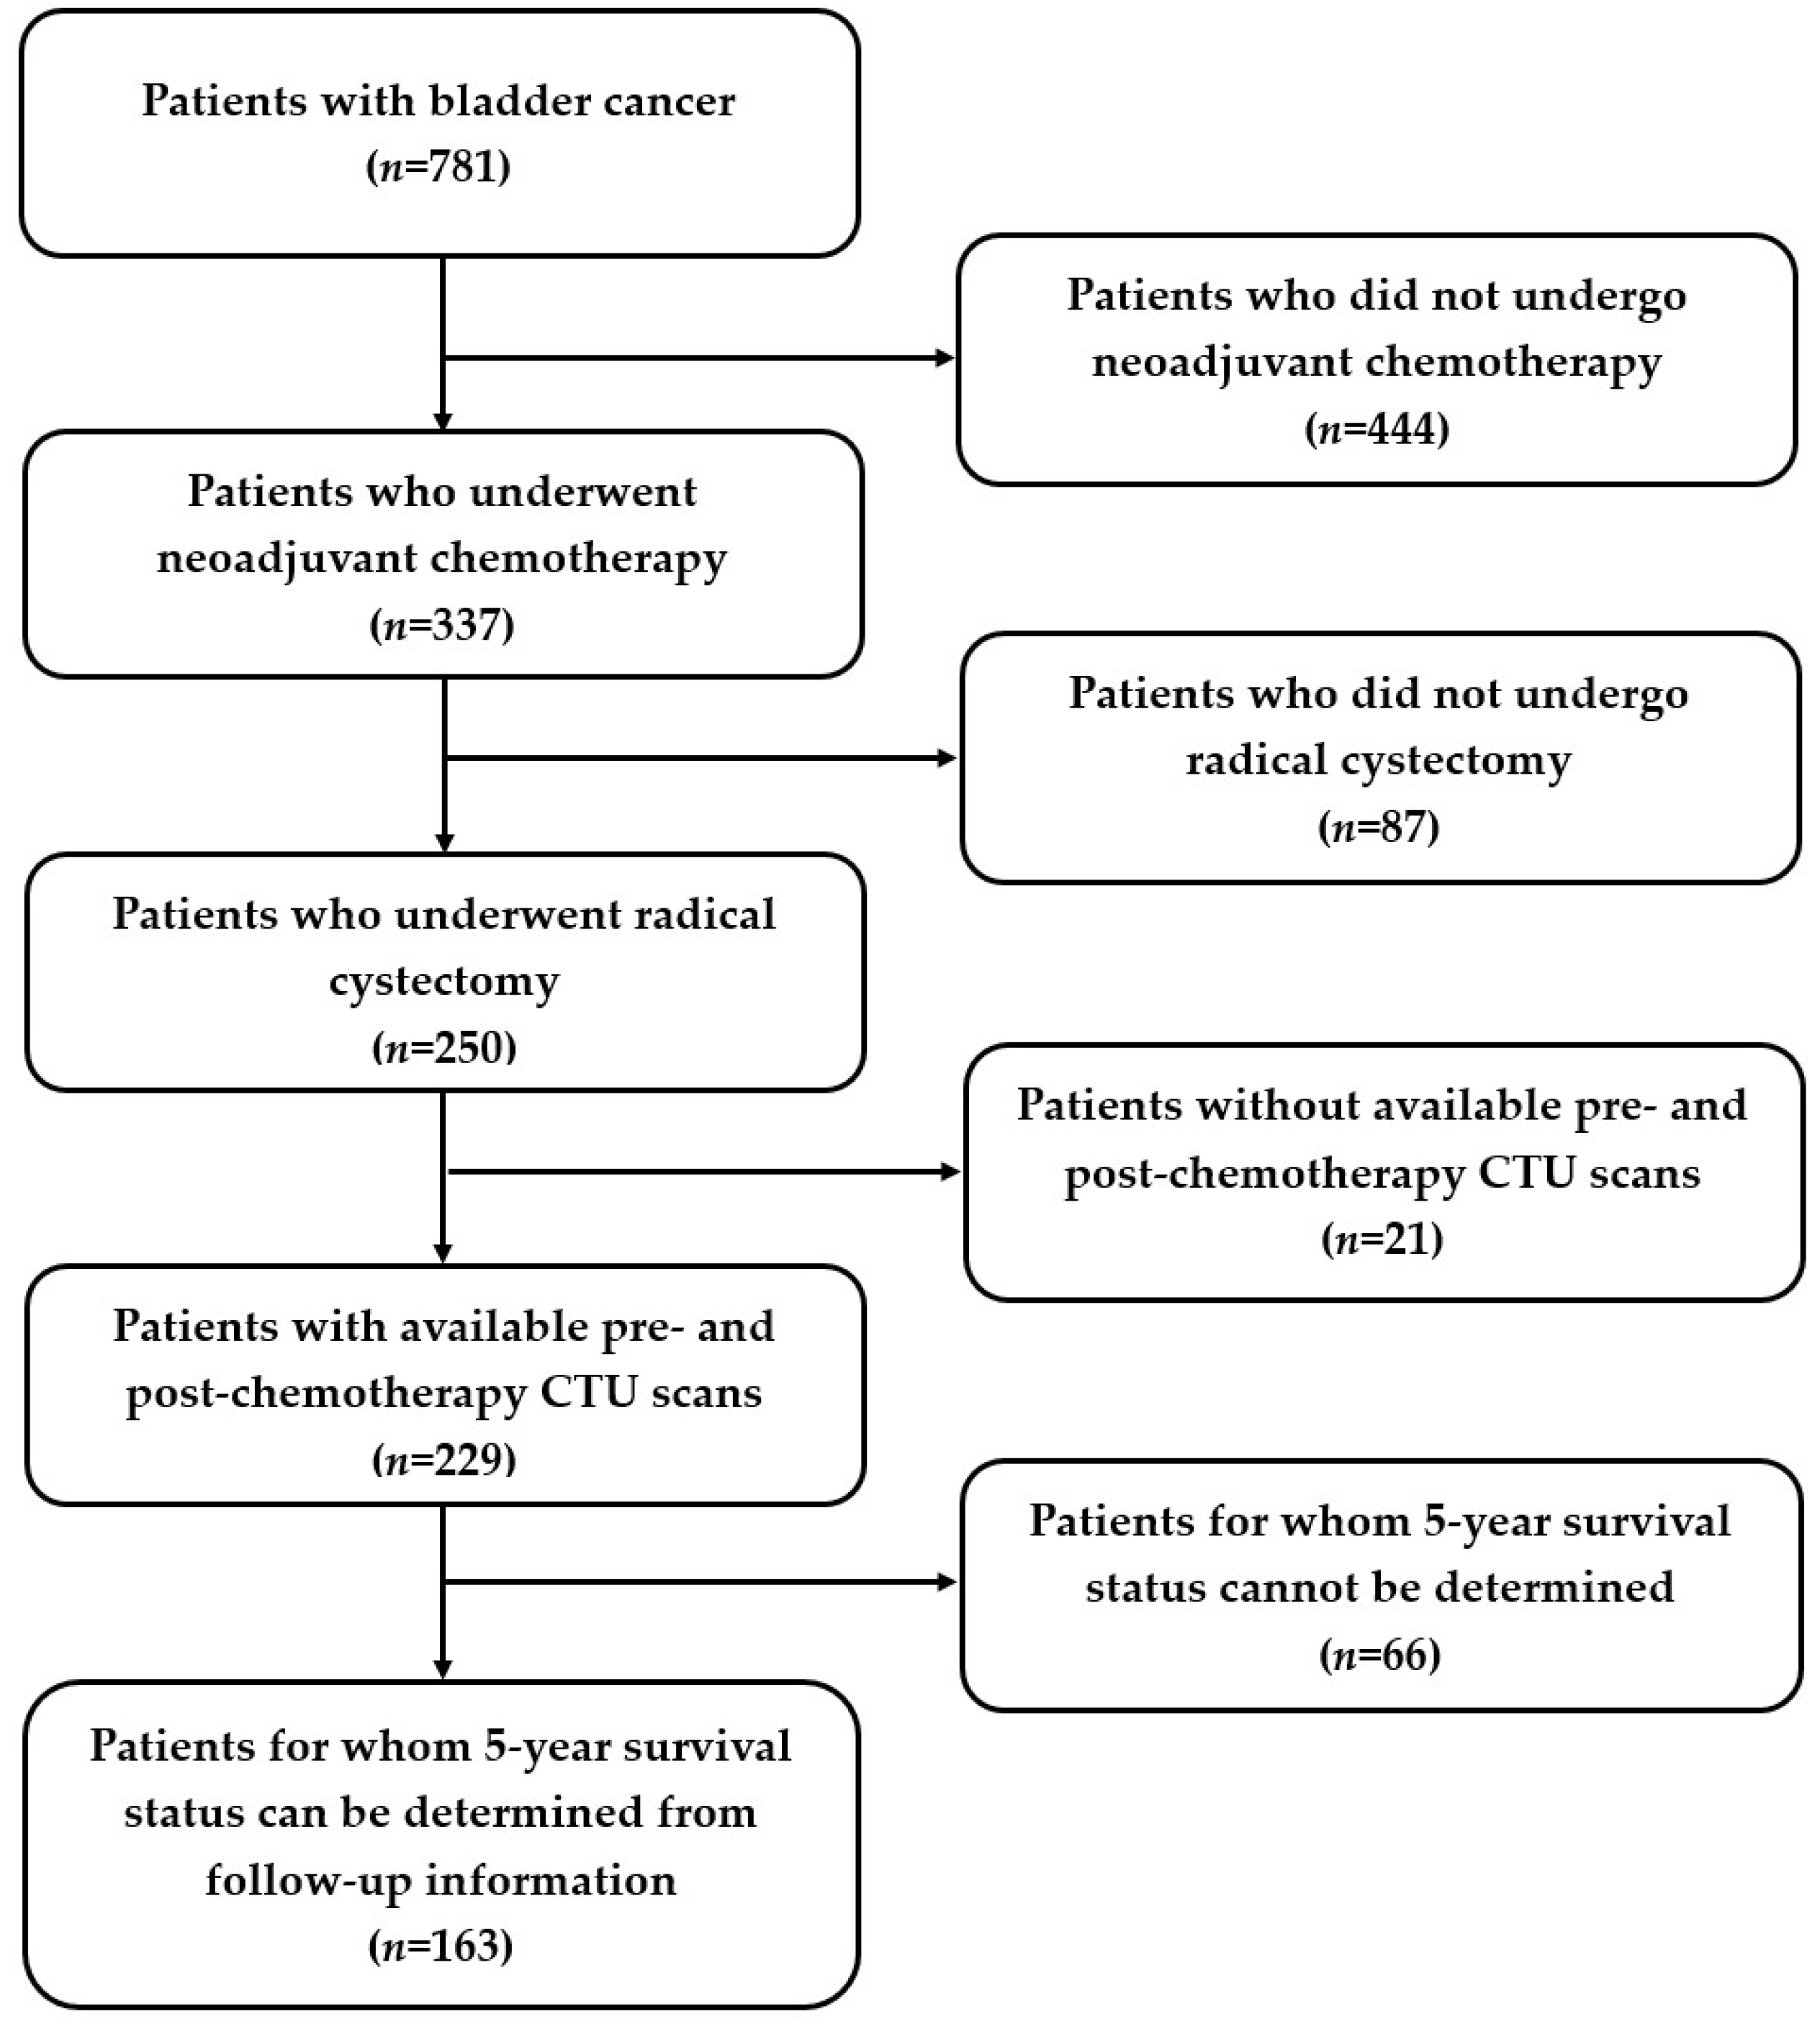

2.1. Patient Cohorts

3.1. Patient Characteristics